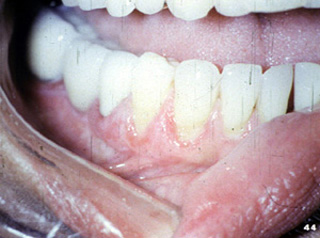

| A menudo

envuelve la encía y tiene una apariencia eritematosa y descamativa. Si

uno mira esta fotografía clínica, pueden verse áreas estriadas

blancas en la unión de la encía marginal con mucosa alveolar.

| Aquí hay

otra vista del eritema de la encía del liquen plano erosivo. |